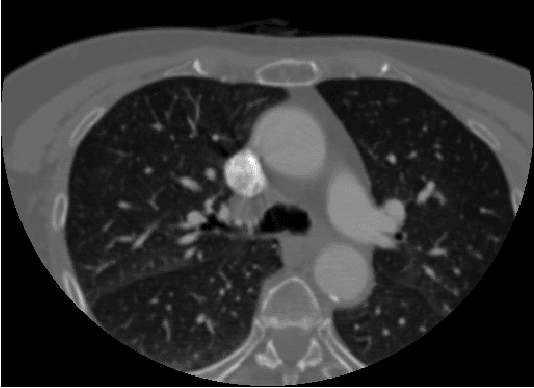

Abstract:Segmentation of medical images using seeded region growing technique is increasingly becoming a popular method because of its ability to involve high-level knowledge of anatomical structures in seed selection process. Region based segmentation of medical images are widely used in varied clinical applications like visualization, bone detection, tumor detection and unsupervised image retrieval in clinical databases. As medical images are mostly fuzzy in nature, segmenting regions based intensity is the most challenging task. In this paper, we discuss about popular seeded region grow methodology used for segmenting anatomical structures in CT Angiography images. We have proposed a gradient based homogeneity criteria to control the region grow process while segmenting CTA images.